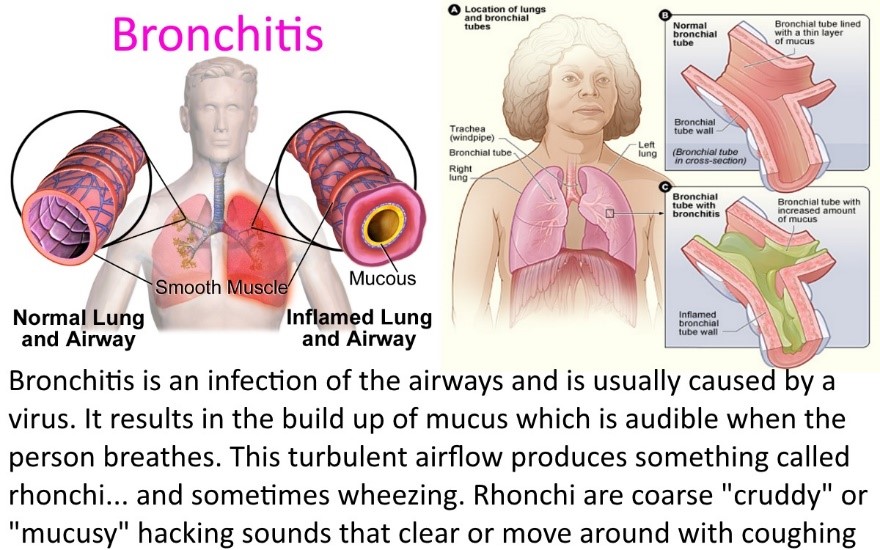

2. Bronchitis:

This is cough arising from difficulty in breathing. It is a disease of the lungs.

2. Bronchitis:

This is cough arising from difficulty in breathing. It is a disease of the lungs.